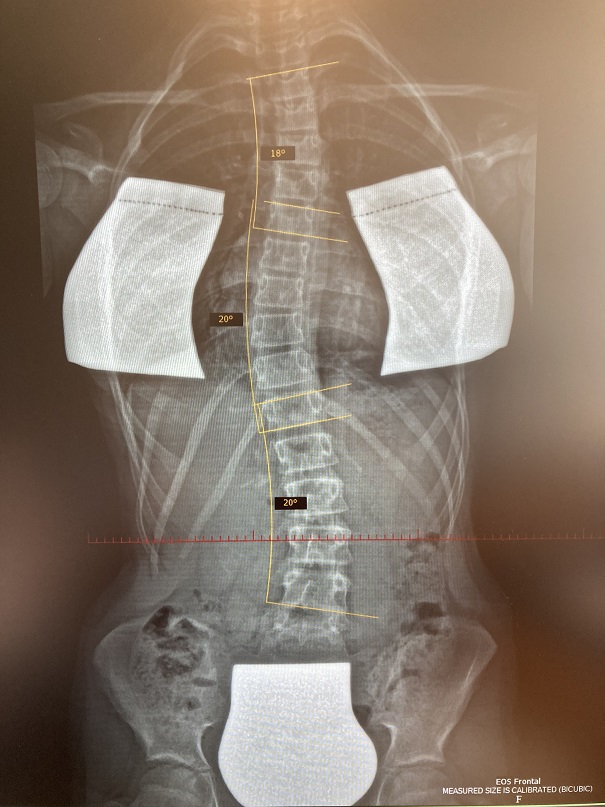

Dann habe ich MRT von LWB veranlasst, um eine Überkorrektur auszuschließen (nach 24 St. ohne das Korsett) und festgestellt, dass meine Tochter noch eine Krümmung im LWB von 20 Grad hat, die sie früher nie hatte.

MRT Bild habe ich an Rahmouni zugeschickt und die Begründung von Herrn Harzer war - "eine leichte Überkorrektur". Der Arzt meine, meine Tochter sollte kein Korsett mehr tragen und beobachten, bis alles wieder zurück kommt und wenn nicht, dann braucht sie ganz anderes Korsett. Zu warten war mit viel zu gefährlich. Ich war sehr frustriert und bin nach Bad Sobernheim gefahren, um noch eine Meinung zu hören. Dort haben wir das neue Röbild gemacht. Alles hat sich bestätigt - meine Tochter hat jetzt drei Bögen anstatt zwei - die alten Krümmungen von Gradzahl fast unverändert. Dazu noch Flachrücken...